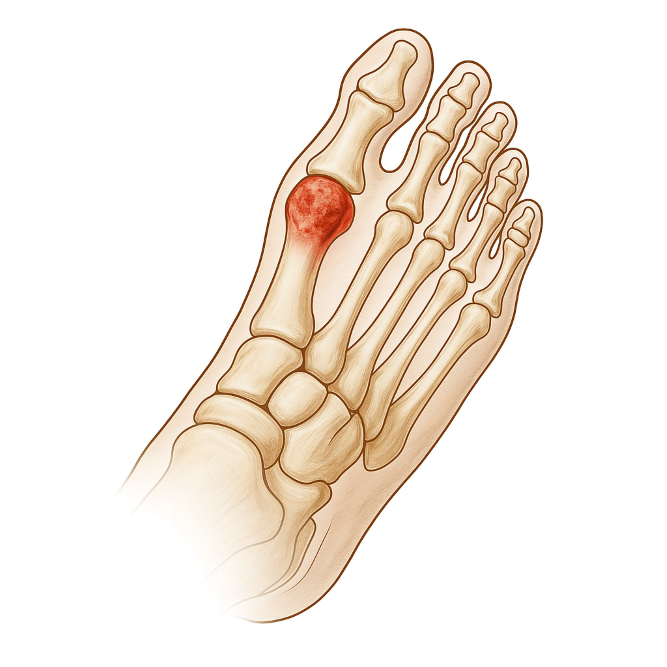

Болезнь келлера мкб